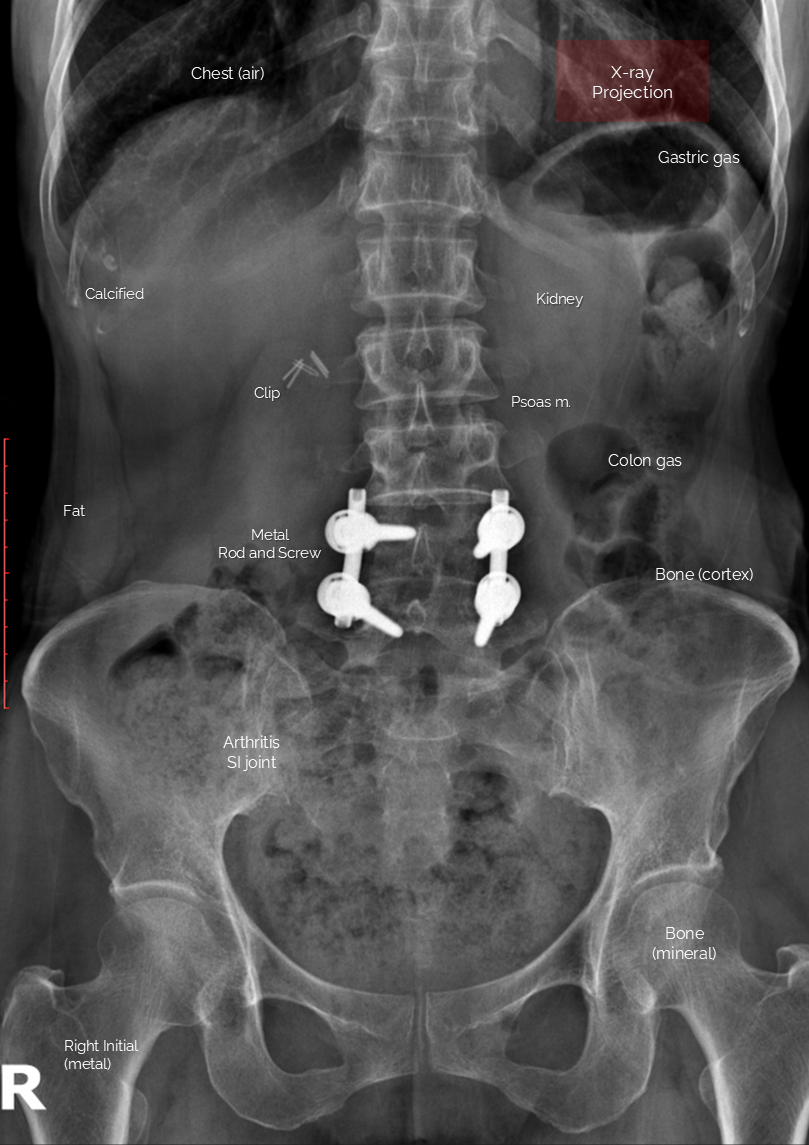

Editorial/Radiography L spine AP by AR Manager 2025. 12. 26. 공유하기 게시글 관리 Acupuncture Radiology 관련글 C spine AP [X-ray anatomy ] Shoulder Detailed MRA of Willis Circle knee MRI anatomy [Coronal, T1]